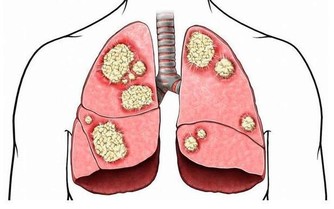

5.蘑菇

蘑菇中含有大量的硒元素,而硒是人體必須的微量元素,

可以提高人體的免疫力,補硒是人們預防肝癌、防治肝病的有效措施。

蘑菇中含有豐富的硒元素,易被人體吸收,是肝癌、腸胃癌等強有力的抑製劑,

所以我們日常生活中可多食用蘑菇。